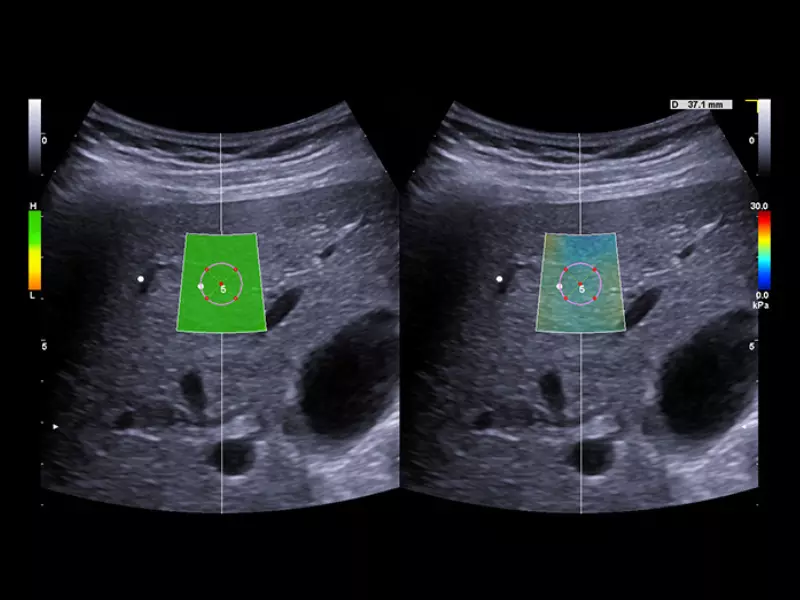

MyLab™9 Platform - QElaXto 2D shearwave elastography in liver

MyLab™9 Platform - QElaXto 2D shearwave elastography in liver